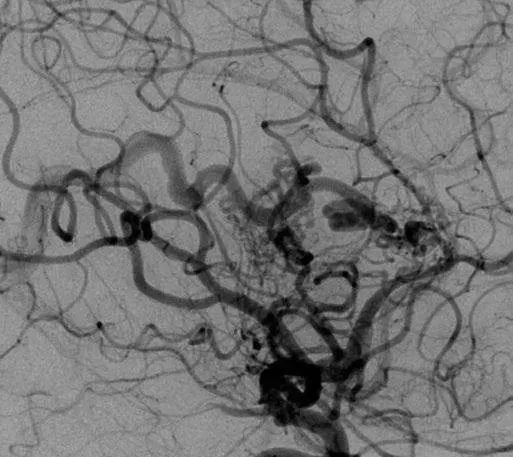

该AVM由ACA/PcaA分支、ACoA穿支和mPChA供血[右侧ICA造影

▼侧位s,前斜位